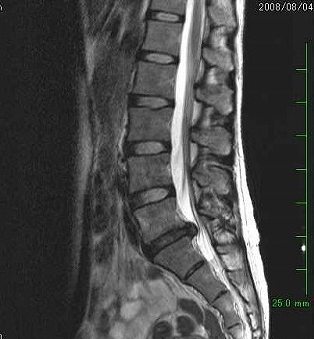

まさにこんな感じ(この写真は別の人のイメージです)

腰の骨と骨の間から黒い不気味なものがぶっくり出ちゃってる。先生と顔をみあわせて、「出ちゃってますね〜」と笑うしかない。

典型的な「椎間板ヘルニア」。薬で痛みを抑えて2〜3ヵ月様子を見て、おさまらなければ「手術」も視野に!!といわれちゃった。